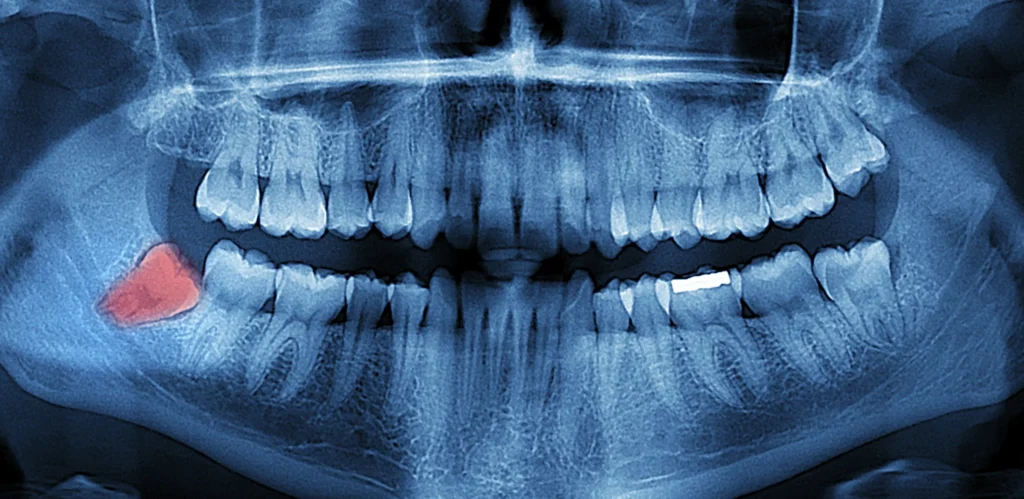

I denti del giudizio si trovano all’estremità posteriore di entrambe le arcate dentarie. Spesso non sono visibili clinicamente, e per individuarli è necessario eseguire una radiografia panoramica (ortopantomografia), che mostra se sono erotti, inclusi o ancora in fase di sviluppo.

- Ortopanoramica o TAC 3D (CBCT) per osservare la posizione dei denti e il rapporto con le strutture nervose e ossee